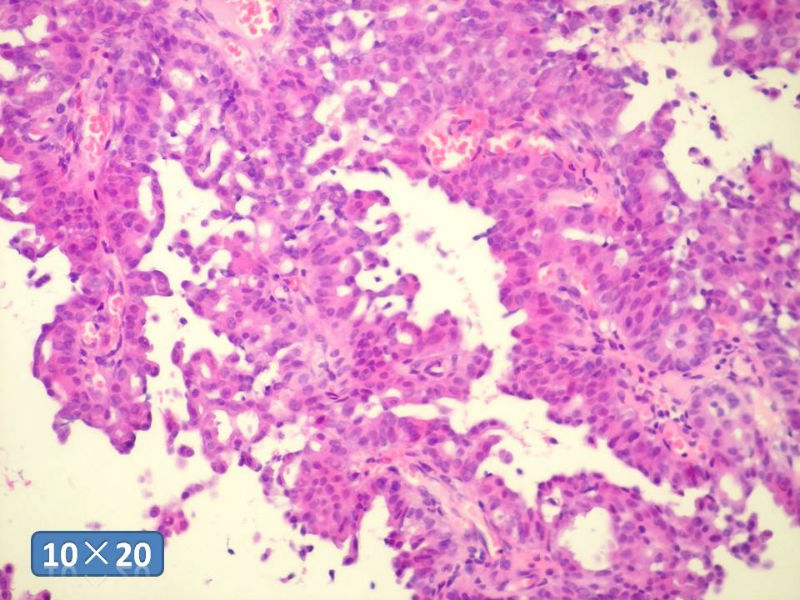

只能说是乳头状瘤

是不是导管内

乳头状瘤 and 导管内乳头状瘤 are the same; Benign lesion.

After you work up and you still cannot be sure it is benign , atypical or maignant lesion, you can call 乳头状lesion.

If this is excisonal case, you should figure out the nature of the papillary lesion.

我的意思就是提醒大家 在不是很确定的情况下 尽量少给自己套枷锁